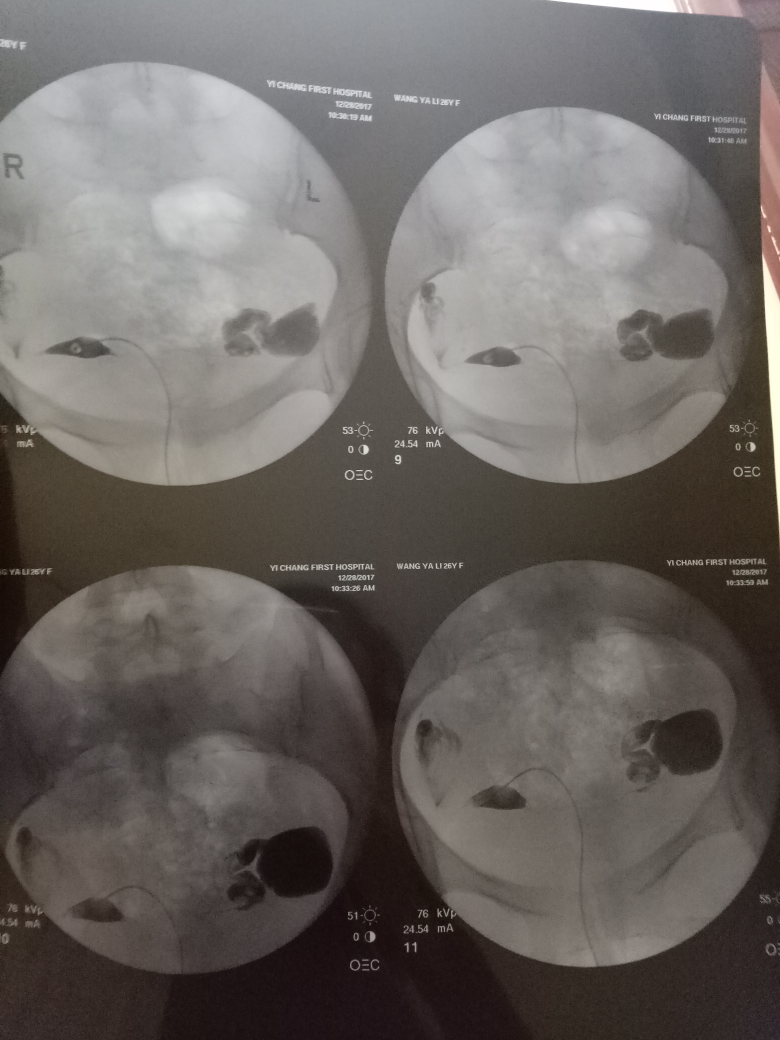

造影后第二個月懷孕的機會與準備。造影是一種醫(yī)學檢查手段,有助于了解身體內部情況。第二個月懷孕的機會取決于多種因素,如個人身體狀況、生育能力、生活方式等。在準備懷孕時,建議保持良好的生活習慣,如合理飲食、適度運動、保持心情愉悅等。還需進行必要的孕前檢查,確保身體狀況良好,為懷孕創(chuàng)造有利條件。造影后第二個月懷孕的機會與準備需根據個人情況而定,建議在專業(yè)醫(yī)生指導下進行。

在現代醫(yī)學中,造影技術廣泛應用于臨床診斷,對于不孕癥的診斷和治療也起到了重要作用,造影是一種通過放射線、超聲波等影像技術觀察人體內部結構和狀況的方法,完成造影后的第二個月,很多夫婦關心是否容易懷孕,造影本身并不會直接影響懷孕,但了解身體情況后,有針對性地進行治療和調理,確實有助于提高懷孕的幾率。

通過造影技術,醫(yī)生可以清晰地觀察到子宮內部環(huán)境,如子宮內膜厚度、輸卵管通暢情況等,若子宮環(huán)境良好,第二個月懷孕的機會將大大增加。

造影技術還可以評估卵巢功能,如卵泡數量、質量等,若卵巢功能正常,有助于排卵和激素分泌,從而提高懷孕幾率。